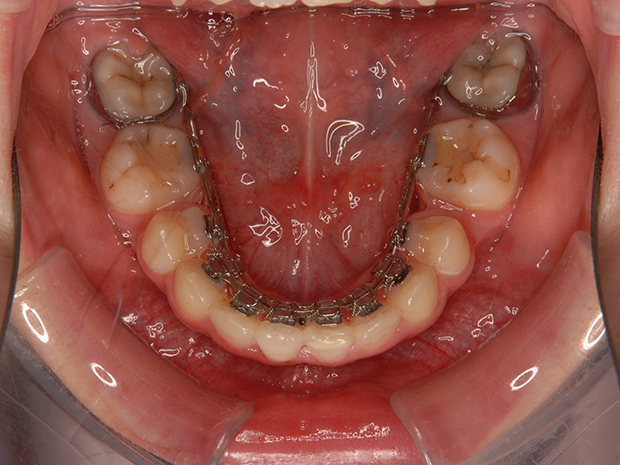

【ハーフリンガル】叢生 抜歯 上顎舌側マルチブラケット装置

| 主訴 |

ガタガタ |

||

|---|---|---|---|

| 診断名 |

右側Angle II級叢生 |

||

| 年齢 | 19歳 | 性別 | 女性 |

| 治療に用 いた装置 |

ハーフリンガル装置 (セミカスタム) | 抜歯部位 | 上顎両側第一小臼歯 下顎両側第二小臼歯 |

| 治療期間 ・回数 |

2年・24回 | 治療費 概算 |

約85万円 (調整料を含む) |

| 治療内容 詳細 |

歯科衛生科に入学し、自分の歯ならびが気になり始めたとのこと。上の歯列のみ舌側矯正(裏側矯正)、下は表側の、ハーフリンガルで治療を行いました。 |

||

| リスク・ 副作用 |

装置による違和感。疼痛、歯根吸収など |

||